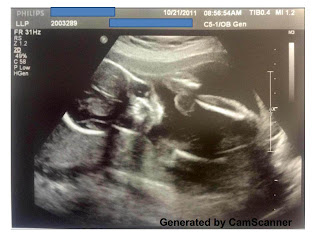

Em bé lúc 20 tuần tuổi

Con đã lớn bằng trái chuối rồi nè. Khi đi siêu âm, Ba thấy con lăn lộn tùm lum, quậy tay chân, có khi còn mút ngón tay nữa. Lúc này Mẹ muốn sự ngặc nhiên cho nên không biết con là con gái hay con trai cưng của Ba Mẹ. Ôi trên đời không có nhiều sự bất ngờ - con trai hay gái, con khoẻ mạnh là Ba Mẹ vui hết biết rồi.